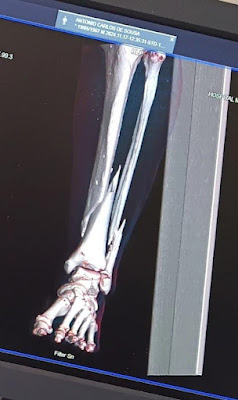

| Imagem do raio x: fraturas na perna esquerda. |

Morador da rua Dr. Souto Maior, bairro Nova Aldeota, desta cidade Ipu-CE, nesta quinta-feira (12/12) solicitou à nossa reportagem para relatar uma situação difícil, bastante delicada, o mesmo sofreu duas fraturas na perna esquerda; tíbia e fíbula, consequência de um acidente de moto.

O sinistro aconteceu no dia 17 de novembro, ou seja, está há quase 1 mês necessitando passar por procedimentos cirúrgicos. Após ser atendido no Hospital Municipal de Ipu, devido a gravidade da lesão, foi encaminhado para Sobral, onde recebeu a recomendação para buscar tratamento em Fortaleza, desde então está aguardando vaga para o devido atendimento médico.